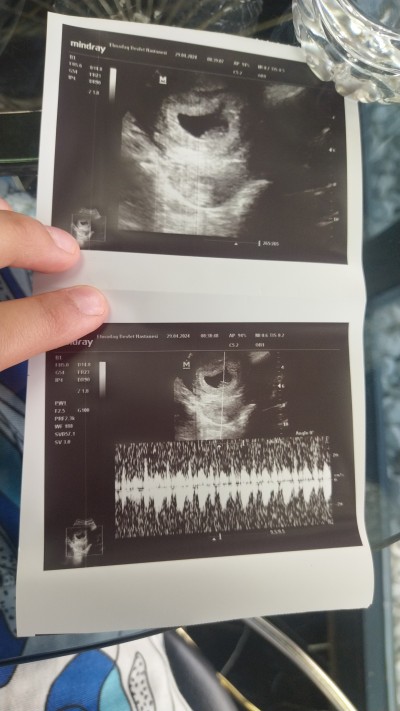

keseye göre cinsiyet tahmini yapabilir misiniz

Gebelik haftası 10